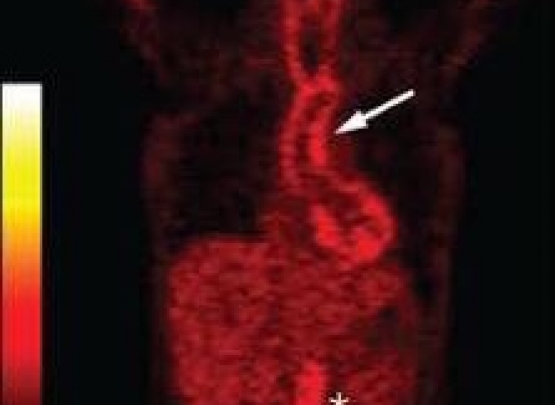

Na fase inicial, como não há sintomas específicos de localização de doença, exame de alta tecnologia, chamado PET-SCAN (foto do artigo), pode trazer alta suspeita da ARTERITE DE TAKAYASU ao demonstrar inflamação na parede de grandes artérias. Em conjunto com outras características clínicas e excluindo-se outras possibilidades, o diagnóstico pode ser feito precocemente.